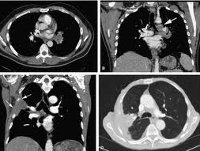

Компьютерная томография легких. Метод лучевой диагностики, основанный на получении изображений тканей и структур легких в виде слоистых срезов толщиной 0,1-1 Использование КТ легких, раковые процессы и их распространенность, повреждение внутригрудных лимфатических узлов, образование средостения, патологические изменения в ткани легких и плевральной полости, легочная артерия, грудная аорта, состояния полой вены верхняя, трахея и бронхи различного калибра. В зависимости от цели исследования с помощью КТ возможно использование «легочного» режима или метода обследования органов средостения; Вы можете улучшить контрастность, чтобы улучшить качество изображения.

При компьютерной томографии легких получают многослойные рентгеновские срезы с шагом от 0,1 до 1 см в результате специального кругового сканирования области грудной клетки узким лучом и последующей компьютерной реконструкции изображения. Использование «легочного режима» при КТ легкого позволяет исследовать междолевые трещины, межсегментные перегородки, крупные, долевые и сегментарные бронхи, легочные сосуды различного калибра. В режиме «средостения» исследуются трахея, сердце, восходящая и нисходящая аорта, верхняя полая вена, легочный ствол и его ветви, а также лимфатические узлы ворот.

Когда КТ легких интерпретируется рентгенологом, изучаются положение и размеры легких, наличие аномалий в них; состояние паренхимы легких в связи с наличием инфильтратов, полостей, образований, быков; воздушность легочной ткани; состояние трахеобронхиального дерева, сосудов, лимфатических узлов, средостения, волокон, плевральных полостей, ребер, мягких тканей грудной клетки. Обычно компьютерная томография легких не выявляет инфильтративных и очаговых изменений в ткани легких. Интраторакальные лимфатические узлы не увеличены. Анатомические структуры средостения дифференцированы без изменений, сердце имеет правильную конфигурацию. Свободной жидкости в полостях плевры и перикарда не обнаружено. Просвет бронхов и трахеи не изменился. Заключение Компьютерная томография легких помогает клиницисту (пневмологу, терапевту, торакальному хирургу, специалисту по туберкулезу, кардиологу) уточнить диагноз и определить последующую тактику.